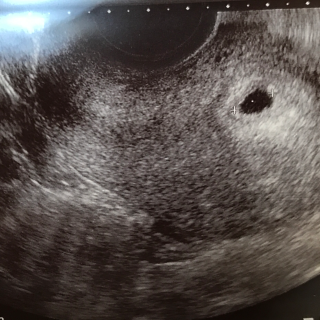

今日胎嚢確認出来ました~! 泣きそうなくらい嬉しかったです、まずは第一段階クリアって感じかな? ただもともと卵巣が腫れていたので大きい黒いのが見えます笑 妊娠初期は腫れてない人でも腫れることがあるそうなので心配いらないそうです。 胎嚢は1.72cm すべてが不順なので胎嚢の大きさからの仮定週数は5w2d もうこの時期から予定日が出るのには驚きました